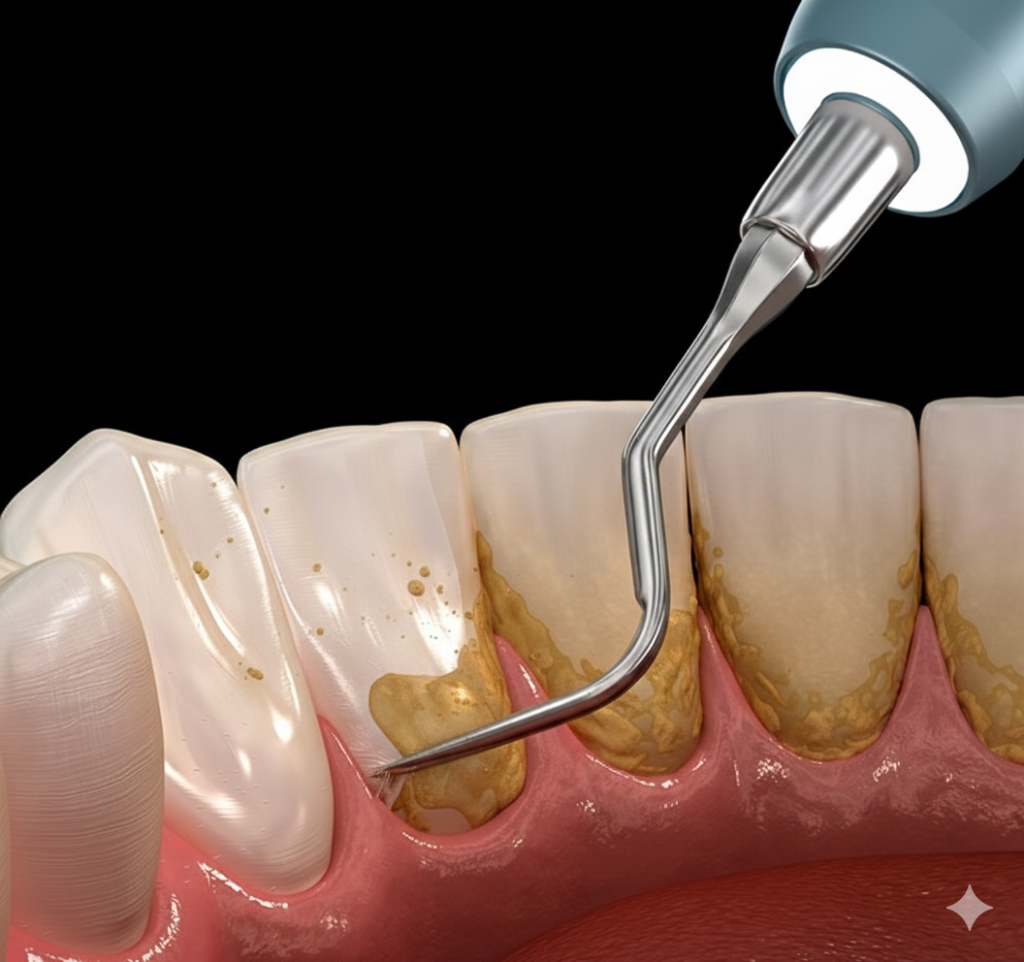

Parodontologie

Parodontologie befasst sich mit der Prävention, Diagnose und Therapie von Erkrankungen des Zahnhalteapparates, insbesondere der Parodontitis. Ziel ist es, entzündliche Prozesse am Zahnfleisch und Kieferknochen zu stoppen, um den Verlust von Zähnen zu verhindern und die langfristige Mundgesundheit zu sichern.